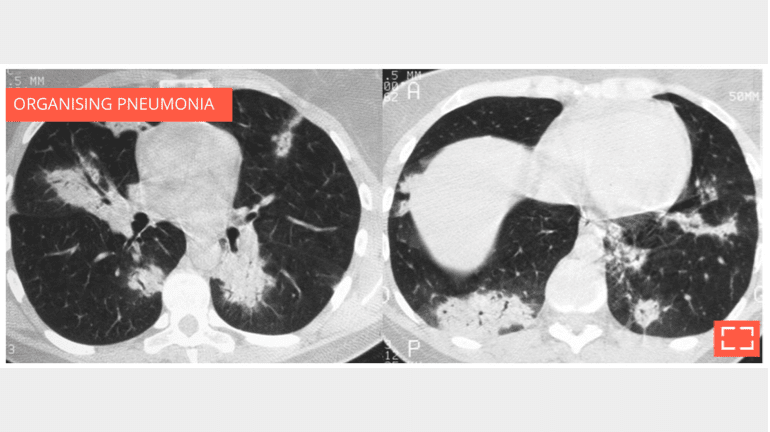

• Chronically evolving pulmonary consolidation (> 8 weeks) that is retractile with air bronchogram.

• The chronic nature of it means a fibroscopy with lavage must be performed.

• If results are negative, a transparietal lung biopsy should be suggested.